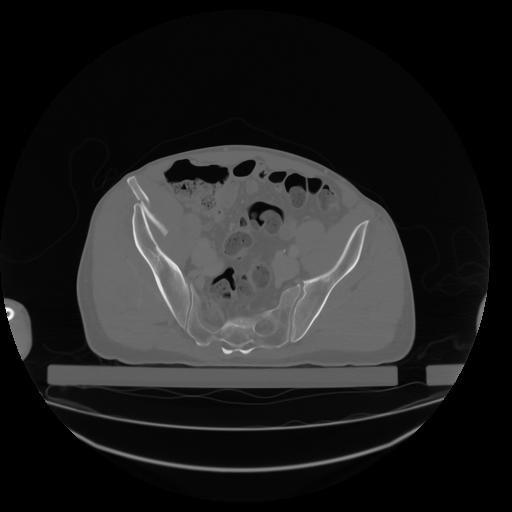

27 CUERPO,CE,Axial,3.0,CUERPO,,